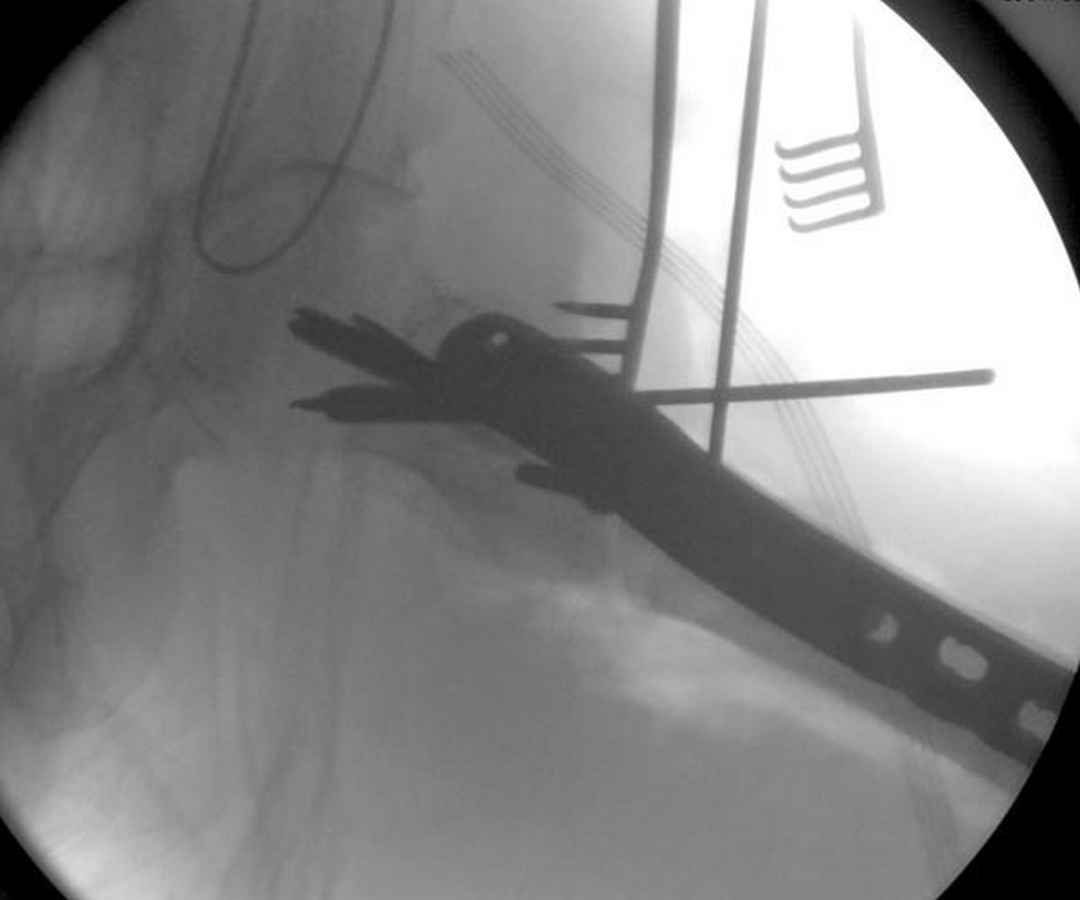

А вот к данным операциям без рентгена, как советует специалисты, я бы отнесся скептически, как раз здесь можно натворить много ошибок, например, от неправильной установки гвоздя мимо шейки до неудовлетворительной репозиции.

судя по картинкам с ЭОПа явно использовались приемы непрямой репозиции под его контролем, а так же интраоперационный ЭОП-контроль положения винтов, без такого контроля операция может ухудшить ситуацию (опять же учтите сроки) т.к. результат буде зависеть в большей степени от искусства хирурга, а не от технологии